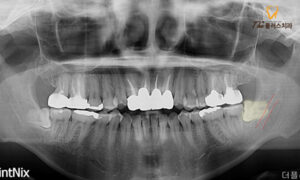

전체적으로 파노라마 사진을 통해

사랑니의 형태를 확인해 본 결과,

환자분께서 말씀해 주신 것처럼

아래 양옆으로 총 2개의 사랑니가

존재하였습니다.

둘 다 누워있는 형태이며 아래턱에

전반적으로 분포하는 신경관인

하치조 신경관과 중첩되어 있는

완전 매복치였습니다.